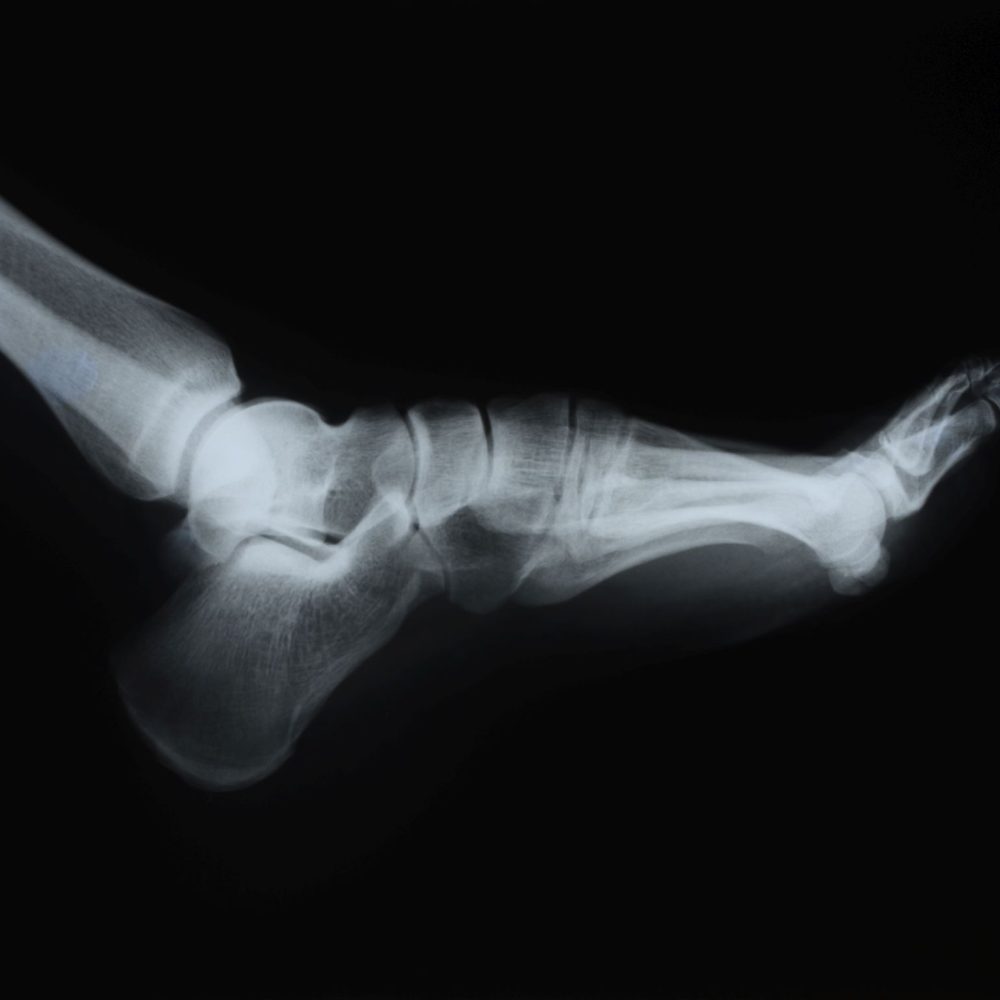

El diagnóstico por imagen en podología combina ecografía (Eco) y radiografías (RX) para identificar con precisión el origen del dolor y planificar el tratamiento más eficaz. La ecografía permite valorar en tiempo real tejidos blandos —fascias, tendones, ligamentos, bolsas serosas y nervios—, detectar fascitis plantar, tendinopatías, bursitis o neuroma de Morton, e incluso guiar infiltraciones cuando están indicadas. Las radiografías muestran con claridad las estructuras óseas y articulares, ayudando a evaluar alineaciones, deformidades (como juanetes o dedos en garra), artrosis, fracturas y la presencia de espolón calcáneo. Trabajar con imagen aporta seguridad diagnóstica: acota la causa real del problema y evita tratamientos generales que no resuelven el origen. Además, permite monitorizar la evolución y decidir si conviene un abordaje conservador, plantillas biomecánicas, fisioterapia o, en casos seleccionados, cirugía.

Usar ecografía y rayos X de forma racional acelera el proceso diagnóstico, reduce la incertidumbre y mejora los resultados clínicos. La ecografía es una técnica dinámica y sin radiación, ideal para valorar el movimiento y el estado real de los tejidos durante la exploración. La RX, con dosis baja y protocolos de protección, aporta una visión estructural imprescindible en deformidades y dolor óseo. Con ambos métodos, el plan terapéutico se ajusta a tu caso: desde pautas de descarga y plantillas personalizadas hasta rehabilitación o cirugía cuando proceda.